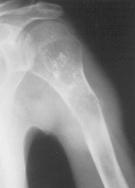

OSTEOSARCOMUL OSTEOGENETIC

Este tumora osoasa maligna cea mai frecventa; apare predominant la baieti între 15 - 25 de ani, se localizeaza la metafiza oaselor lungi ale membrelor - mai ales la cele din apropierea cartilajului de crestere (aproape de genunchi, departe de cot), oasele bazinului, omoplat, rar la oasele craniului, vertebre, coaste.

De la metafiza, tumora se extinde atât spre diafiza cât si spre epifiza si, mult timp respecta articulatia.

OSTEOSARCOMUL OSTEOLITIC apare ca o zona de osteoliza cel mai frecvent centrala sau periferica cu contur neregulat care rupe corticala si desprinde periostul sub forma de spicul (pintene sarcomatos Kodman).